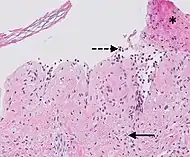

Kaposi’s sarcoma in patch stage The patch stage typically shows irregular proliferation of jagged vascular channels in the dermis below an integral epidermis. The so-called promontory sign is sometimes found in patch stage lesions and denotes vascular spaces surrounding pre-existing blood (see image).[23]

vessels